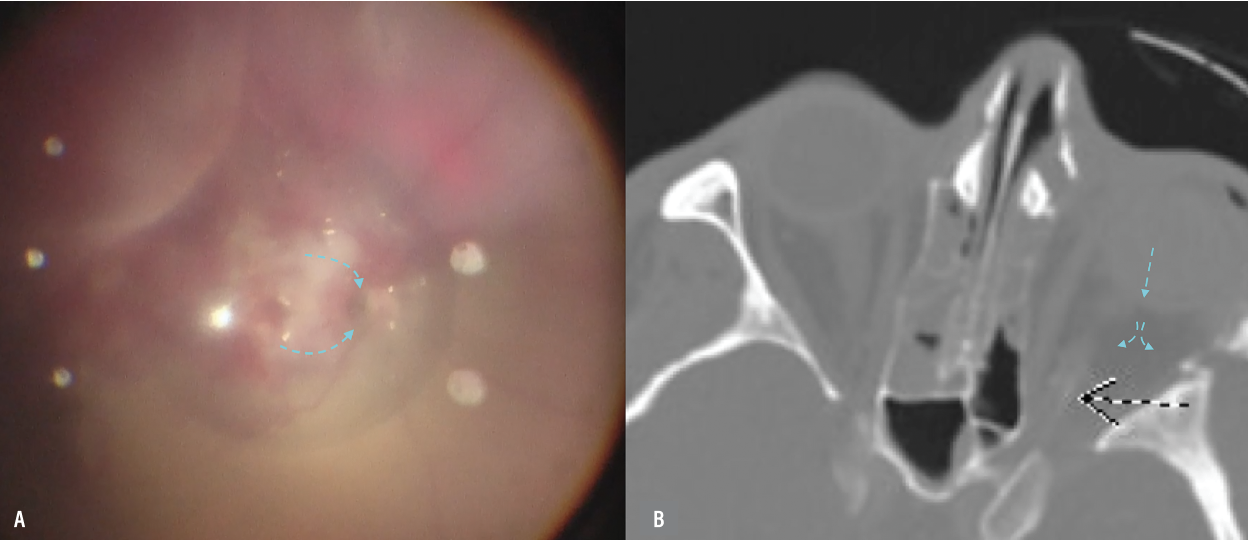

A) Intraoperative imaging depicts the defect located at the temporal edge of the optic nerve and the route of perfluorooctane (PFO) migration. B) Postoperative computerized tomography scan shows the PFO in the orbit (blue arrows) with possible hyperintensity of the distal optic nerve. |

Due to our patient’s medical status, we were unable to obtain a postoperative MRI, but the CT scan images demonstrated extraocular migration of PFO with tracking along the optic nerve. These findings supported our belief that an optic nerve avulsion injury was the likely culprit.